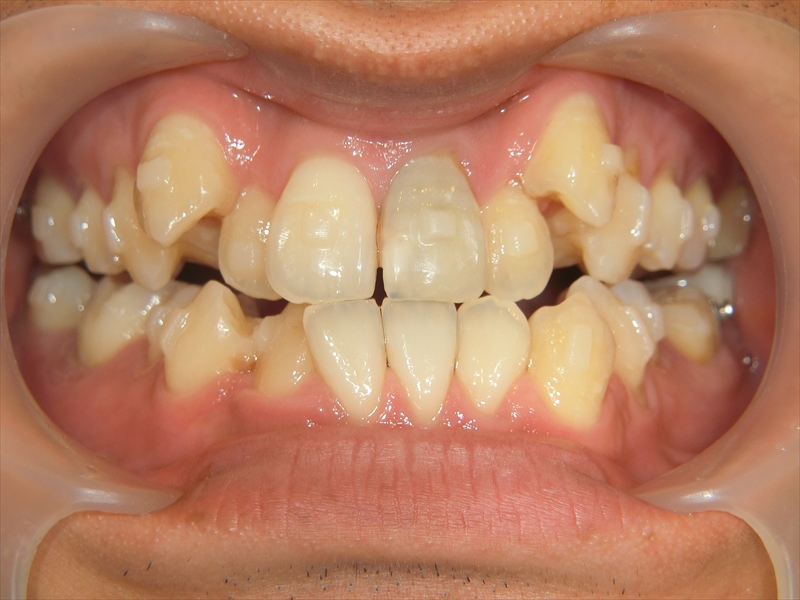

この症例は、20代男性の大人の矯正治療です。

上の歯は歯が並ぶスペースが足りず、八重歯を含むガタガタした歯並びになっていました。

下の歯は、受け口気味で、さらに右下の前から2番目の歯が1本足りない状態でした。

また、歯並び全体がお顔の中心よりも右にずれており、噛み合わせも左右で違っていました。

右側では下の歯が前に出すぎており、左側では逆に下の歯が少し後ろに下がっているという、左右でバランスの取れていない噛み合わせでした。

治療前後 写真